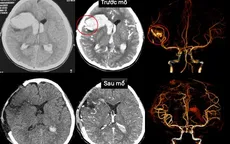

VTV.vn - Bệnh viện Đa khoa Quốc tế S.I.S Cần Thơ vừa phẫu thuật cứu sống bà N.T.V (66 tuổi, ở Bạc Liêu) bị vỡ mạch máu não khi đang hát karaoke.